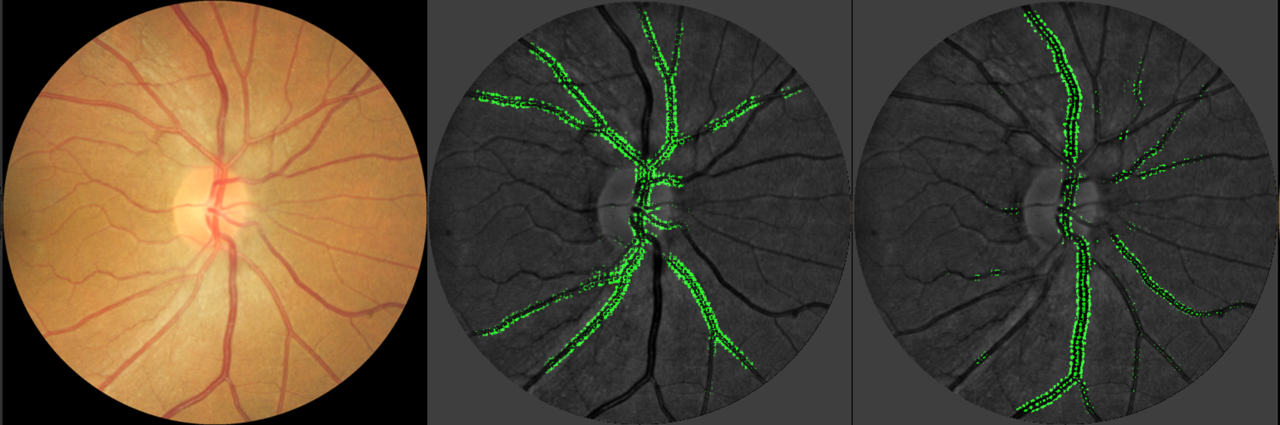

The retinal blood vessels, which are accessible to direct non-invasive visualization, share similar anatomical and physiological characteristics with microcirculation in the body. For over three decades, many researchers have sought to measure retinal blood vessel changes from photographs of the retina using imaging software, typically with human assessors. In our recent study in Nature Biomedical Engineering, we developed an artificial intelligence (AI) deep learning convolutional neural network (CNN) to measure the calibre of retinal blood vessels. We were able to test this AI system in diverse multi-ethnic, multi-country datasets in more than 60,000 retinal images. We found a high correlation of the AI system with validated human measurements, and demonstrated comparable (or stronger) relationships of AI-measured retinal vessel calibre with classic CVD risk factors (e.g., blood pressure). We were also able to demonstrate that AI-measured retinal vessel calibre could be predictive of incident CVD events.